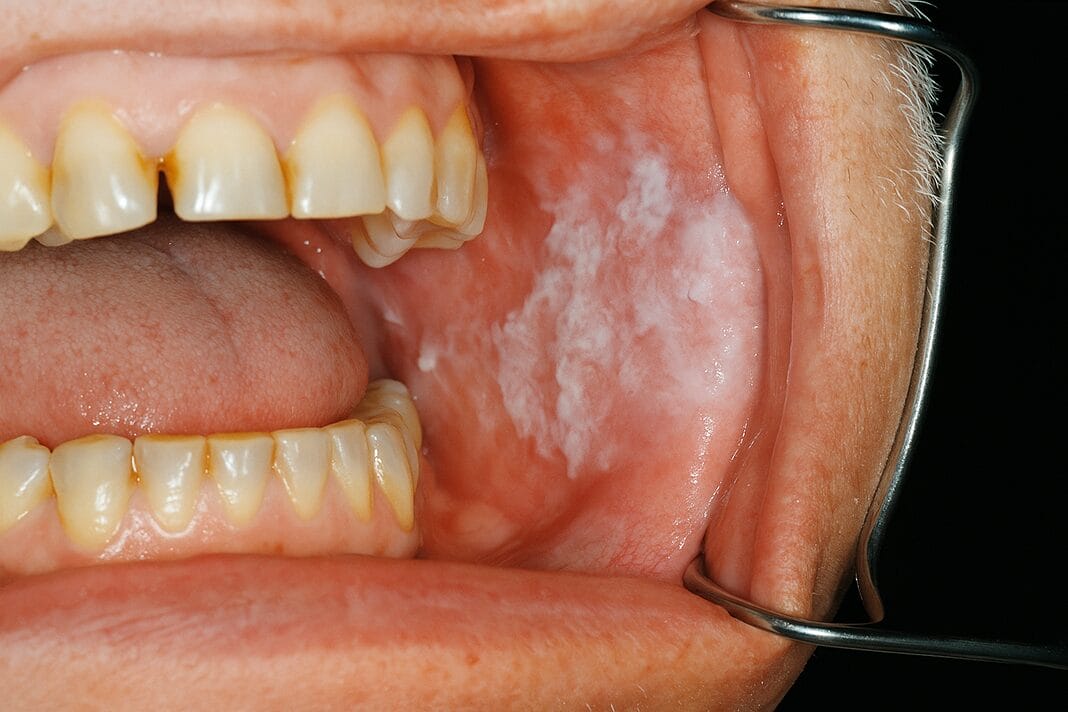

3. Oral leukoplakia is the most prevalent potentially malignant lesion of the oral mucosa, with up to 62% of oral squamous cell carcinomas related to this condition.

Oral leukoplakia is the most prevalent potentially malignant lesion of the oral mucosa, with up to 62% of oral squamous cell carcinomas related to this condition. The etiology is unclear, but some research indicates an association between oral leukoplakia and tobacco, alcohol, sanguinaria (bloodroot plants), ultraviolet radiation, trauma, betel quid chewing, genetic factors, and microorganisms.1

Oral leukoplakia presents as an irreversible, non-scrapable, slightly raised white plaque that may have a wrinkled, leathery to "dry or cracked mud" appearance. These lesions are divided into two types: homogenous and non-homogenous.1

The homogenous type has a smooth, regular, whitish surface with clearly defined margins. Non-homogenous presents with erythematous areas and can be nodular, erosive, ulcerated, or have verrucous growths. It can be localized or widespread, affecting the buccal mucosa, lips, and gingiva.1